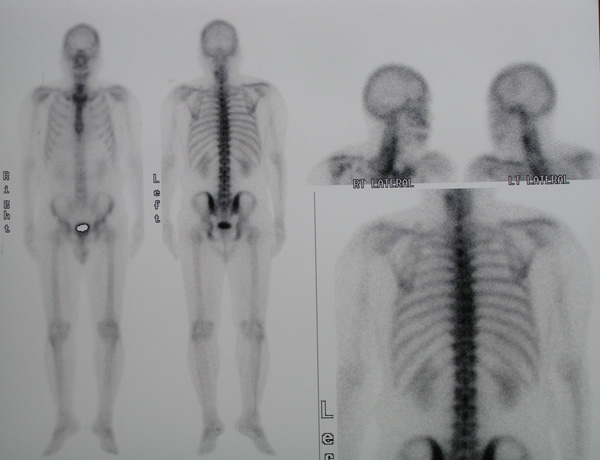

Bone scan on 2 June 2010 showed a mildly increased tracer activity in the mid to lower cervical spine, T4 and T5 vertebrae. No conclusive scan evidence of bone metastasis.

A bone scan was also performed on 6 October 2010.